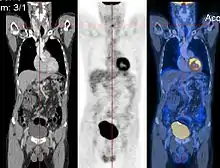

Image registration is a process that searches for the correct alignment of images.[15][16][17][18] In the simplest case, two images are aligned. Typically, one image is treated as the target image and the other is treated as a source image; the source image is transformed to match the target image. The optimization procedure updates the transformation of the source image based on a similarity value that evaluates the current quality of the alignment. This iterative procedure is repeated until a (local) optimum is found. An example is the registration of CT and PET images to combine structural and metabolic information (see figure).

- Combining complementary information from different imaging modalities. An example is the fusion of anatomical and functional information. Since the size and shape of structures vary across modalities, it is more challenging to evaluate the alignment quality. This has led to the use of similarity measures such as mutual information.[19]